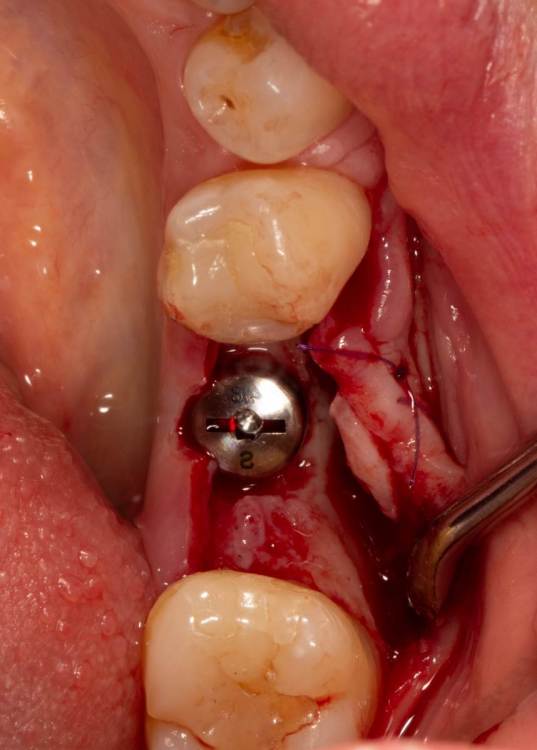

Женька Опубликовано 19 июня, 2023 Поделиться Опубликовано 19 июня, 2023 Здравствуйте, коллеги. Примерно с нового года начал ставить ТЛ имплантаты Дентиум. Что-то под заглушку (не поймал торки, представляете?). Что-то на низких формирвателях. И вот пришла пора протезирования, но отпустить к ортопеду не подготовив десну - не получается. Создал сам себе проблем, сегодня вот исправлял. Получилось неплохо? 3 Ссылка на комментарий

Женька Опубликовано 20 июня, 2023 Автор Поделиться Опубликовано 20 июня, 2023 @АнтонТЛТ мы же позиционируем платформу относительно зенита? Есть ли разница тогда, какой имплантат мы выбираем? Вообще весь смысл здесь был заложен в том, что толщина гребня была не очень. Хотелось поставить тонкий имплантат 3.6. Но рисковать тонкой платформой не хотелось, поэтому выбор пал на 4.8 платформу ТЛ и тело имплантата 3.6 1 Ссылка на комментарий